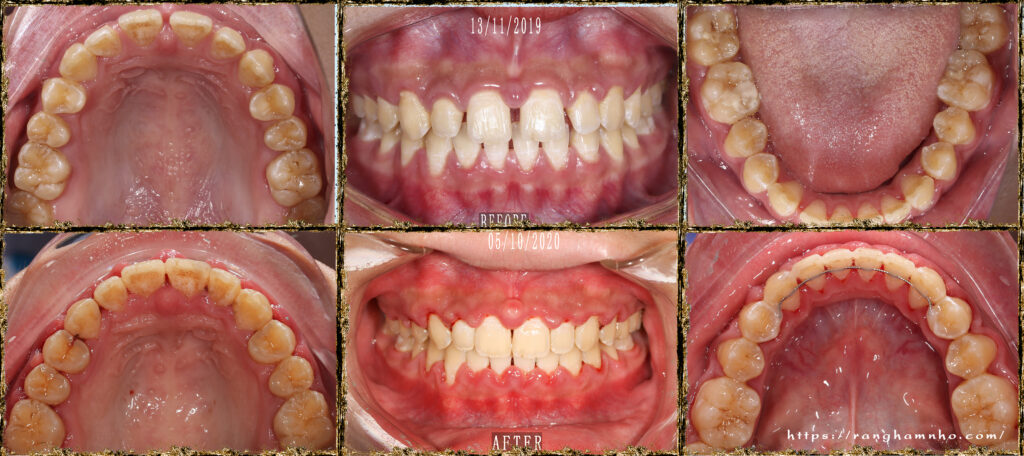

Bệnh nhân nữ sinh năm 2004 đã được điều trị tại 1 cơ sở nha khoa khác hơn 1 năm nhưng không cải thiện được tình trạng răng thưa, tình trạng việm lợi & hôi miệng cũng làm người nha BN lo lắng, không yên tâm trong công tác điều trị, cuối cùng có những khúc mắc ngoài lề giữa bác sĩ và người nhà nên BN không tiếp tục điều trị ở cơ sở cũ mà chuyển cơ sở điều trị khác.

Đánh giá: một trường hợp khe thưa răng cửa giữa hàm trên rất hay gặp trên lâm sàng, nếu không đánh giá đúng tính hình có thể rất dễ bị tái phát do vấn đề khớp cắn, khi đong khe thưa không căn chuẩn thì đường giữa hai răng cửa hàm trên sẽ lệch so với đường giữa mặt (lệch đường giữa hàm trên) và đường giữa hàm dưới có thể không thẳng đường giữa hàm trên.

Phương án: đóng khe thư nhóm răng cửa trước, đánh giá cẩn thận khi đóng khe thưa răng cửa giữa hàm trên và hàm dưới kĩ lưỡng, đưa đường giữa về vị trí chuẩn, sau đó mới đóng hết khoảng và tinh chỉnh khớp cắn.

Kết quả: đường giữa đẹp, khớp cắn ổn sau 1 năm điều trị. Tuy nhiên, BN đeo niền lâu & yếu tố tuổi dạy thì làm tình trạng việm lợi- phì đại lợi tồn tại. BN được tháo mắc cài, hướng dẫn CSRM kĩ lưỡng kèm mát xa lợi, đeo hàm duy trì máng trong. Kết qảu tái khám rất ổn sau 6 tháng.